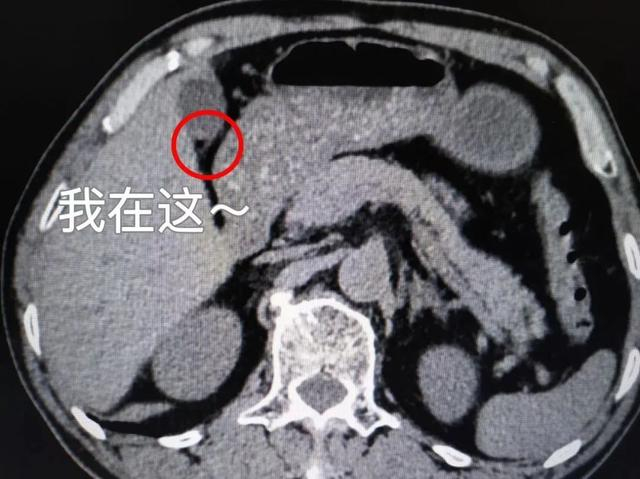

三种类型的结石CT图像

胆囊阴性结石

就是等密度胆固醇结石(CT上表现与胆汁密度一致)或低密度胆固醇结石(CT上表现为低密度):CT表现为低密度、等密度充盈缺损,单发或多发,类圆形或多角形;CT值在40Hu以下,变换体位结石位置有变动,少数与胆囊壁粘连者不能移动。